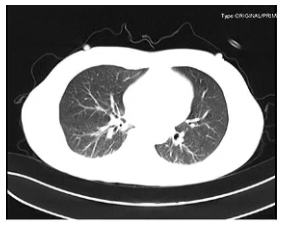

辅助检查:入科第2天行气管镜检查示左肺通畅,右肺大量黄色脓痰(35 ml)(图1)。再行肺部超声检查示右肺点有明显的碎片征,提示右肺实变(图2)。膈肌超声检查示患者右侧膈肌不动,对EDP无反应(图3)。

图2 肺部超声检查

各项检查均提示患者右肺存在问题,且患者右侧膈肌对EDP无反应,是何原因?

查阅文献发现,高位颈髓病变可导致肺实变和肺不张,机制为:①外周交感兴奋性降低;②呼吸肌力降低;③咳嗽反射降低(图4)。故进一步考虑此例患者为外周神经疾病病变引起的单侧膈肌不动,目标为气道管理、改善肺充气、膈肌管理。